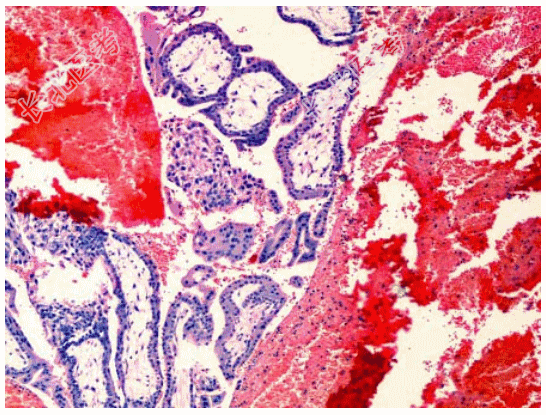

- [材料题] 患者女性,36岁,停经50余天,腹痛一天,后穹窿穿刺少量新鲜血,术中见右输卵管壶腹部膨大并有活动性出血。切除右输卵管,显微镜下所见如图。临床诊断为输卵管妊娠。

- 简答题3、该疾病镜下改变表现为?